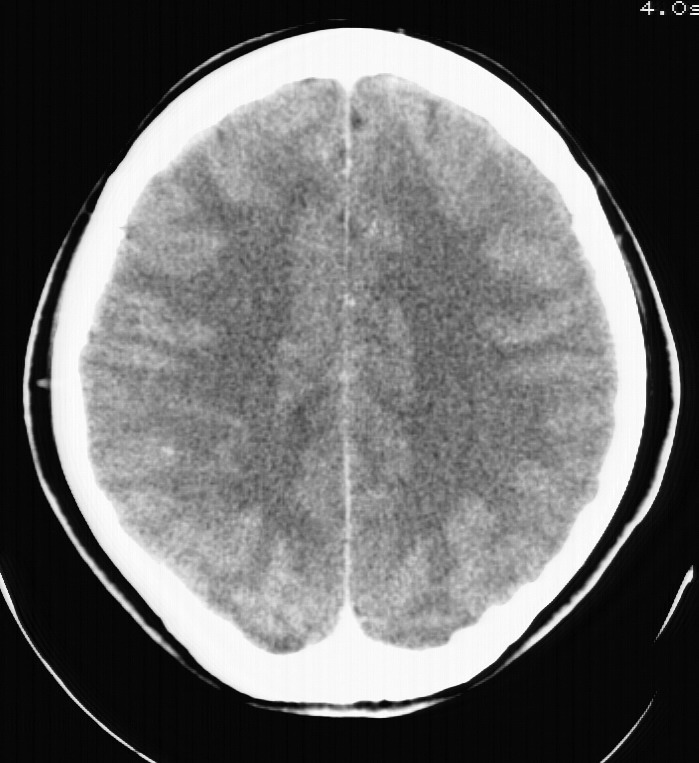

标题: CT5853:右额叶上部占位请会诊

女,34岁,自述头晕胀2年,近期感精神恍惚,无发热,实验室检查阴性。

右顶叶靠近脑表面圆形低密度灶,周围无水肿及占位效应,增强病灶无明显强化,考虑:右顶叶低分级星型细胞瘤。

右额叶上部皮质区见类圆形低密度区,边界不清,无强化,无钙化。

支持大多数战友的意见,1级星形细胞瘤。